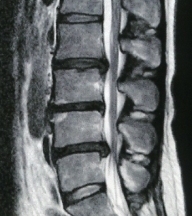

2ヶ月半ぶりに病院でMRI画像を撮ってもらった。

毎日おとなしく療養しているんだから、もっと引っ込んでくれているものかと思ったのに、

ほとんど変わっていなかった。

医者には、「そんなに早く凹まないよ。」って言われたけど。

3ヶ所もあるから時間がかかるみたい。

炎症が起こってる部分もまだ白く写ってるし(x_x;)

はぁ~~当分は辛抱の日々が続くって感じです。